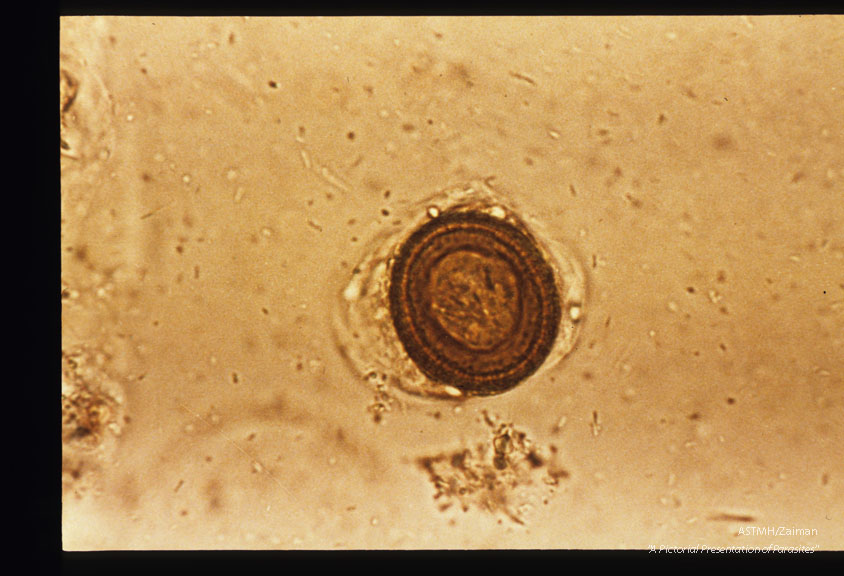

Egg in stool. Iodine stained.

Taenia

Description: Egg in stool. Iodine stained.